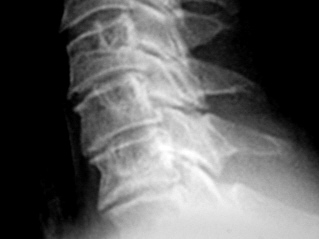

Иллюстрации 1, 2, 3. Определяется «выпрямленность» шейного лордоза, неравномерное сужение межпозвонковых щелей в сегментах С2-С3, С3-С4. Резкое сужение межпозвонковых щелей в сегментах С4-С5, С5-С6, С6-С7, с выраженным субхондральным склерозом тел позвонков, неровностью замыкательных пластинок, образованием остроконечных остеофитов по передней поверхности тел позвонков. В дугоотросчатых суставах определяется сужение суставных щелей с выраженным субхондральным склерозом. На иллюстрации 2 хорошо дифференцируется остеосклеротическая перестройка тел С4, С5, С6, С7, как компенсаторная приспособительная реакция, в результате анатомической и функциональной несостоятельности межпозвонковых дисков.